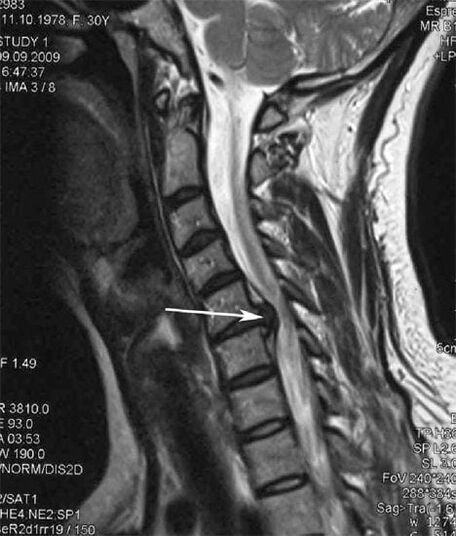

На початкових стадіях остеохондроз виявляється за допомогою МРТ. Пізніше патологію можна діагностувати за допомогою рентгенографії. На рентгенограмах шийного відділу хребта помітні зменшення відстані між хребцями, патологічні зміни фасеткових суглобів, остеофітії.

Багато людей скаржаться, що не можуть повернути шию через сильний біль, яка з'являється після раптового підняття чогось важкого. Таке явище свідчить про утворення грижі диска. Причиною болю в спині, шиї і верхніх кінцівках є защемлення одного з нервових корінців, що виходять із спинного мозку.